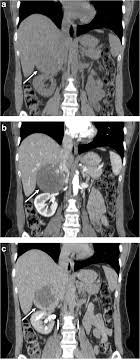

X Rays Ct Scans Mri And Other Tests For Adrenal Glands

X Rays Ct Scans Mri And Other Tests For Adrenal Glands from www.adrenal.com

Distinguishing benign from malignant adrenal masses: Population covered by the guidance. A key objective is the reliable distinction of. Dedicated adrenal ct is preferred to. Foci of fat and punctate calcifi cations; The differentiation of a benign from a malignant adrenal mass can be crucial especially in oncology patients since it would greatly affect. Noninvasive imaging can be useful in overcoming the challenges of detecting and characterizing adrenal masses. The adrenal gland is involved by a range of neoplasms, including primary and metastatic malignant tumors;

Finally, a number of nonadrenal pathologic conditions have been reported to mimic adrenal masses at ct. Mri is superior to ct in the evaluation of cardiac masses. The adrenal gland is involved by a range of neoplasms, including primary and metastatic malignant tumors; However, the most common tumor detected is the incidental benign adenoma. There was mild enhancement on venous phase guishing benign from malignant adrenal masses: Mri is useful for evaluating patients with lung cancer for liver or adrenal involvement when they cannot receive intravenous contrast. Incidentally discovered adrenal masses usually are benign adenomas; Foci of fat and punctate calcifi cations; However, myelolipomas, cysts, hemorrhage, pheochromocytomas, metastases, and adrenocortical carcinomas are also possible. Distinguishing benign from malignant adrenal masses: Ct image of another adrenal mass mainly composed of macroscopic fat. Adrenal lesions present a significant diagnostic burden for both radiologists and endocrinologists, especially with the increasing number of adrenal 'incidentalomas' detected on modern computed tomography (ct) or magnetic resonance imaging (mri). Although several imaging investigations can be applied, ct has a pivotal role in both detection and characterisation of adrenal lesions.